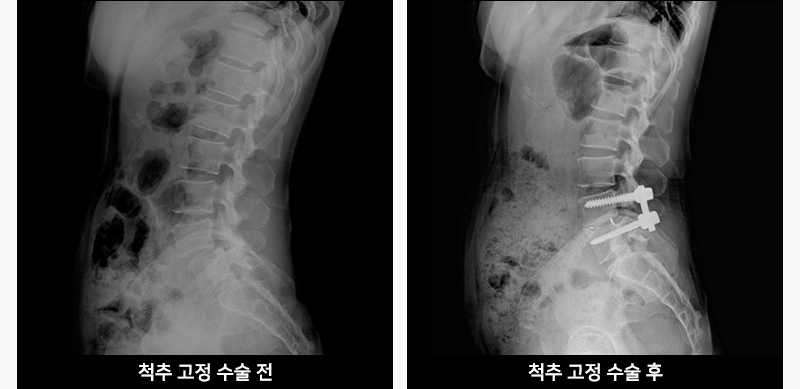

척추고정술이란?

신경압박이 심하거나 척추체 사이가 어긋난 경우는 광범위한 신경감압이 필요합니다.

이때 척추 뼈 사이에 고정기기를 이용하여 척추를 안정감 있게 고정하고 강화하는

치료방법을 척추고정술이라고 합니다.

척추를 고정하면 치료 후 유연성이 떨어지거나 인접 부위에 퇴행성 변화가 일어나는

단점이 발생하지만, 광범위한 신경감압으로 치료를 상당히 효과적으로 할 수 있고

수술부위의 재발이 없습니다.